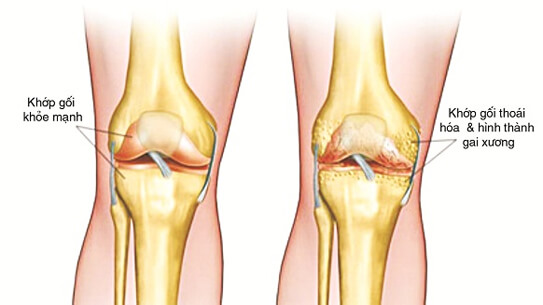

- Massage xông nóng vùng đầu gối, các túi khí ôm sát vùng khớp gối như những bàn tay mềm mại nhẹ nhàng tì vuốt vào nhuwgx vị trí đau nhức. Duy nhất, độc đáo và rất khác biệt của Dr.Care giúp xua tan đau nhức vùng khớp gối nhanh chóng. Nhẹ nhỏm thư giãn cả người, tay chân như được phục hồi hoàn toàn, giúp các khớp gối hoạt động trơn tru êm ái. Không còn lo sợ đau nhức khớp gối tái phát, tình trạng thoái hóa khớp được đẩy lùi.